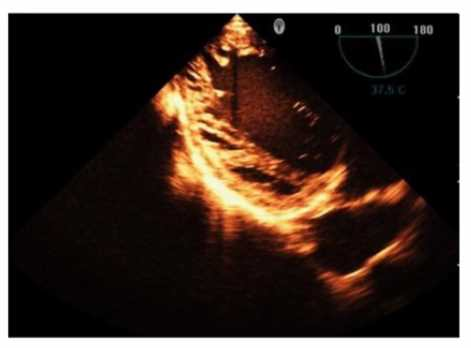

Which is the most likely abnormality represented in these images from a 48-year-old man with shortness of breath?

1. Loeffler syndrome

2. Hypertrophic cardiomyopathy

3. Left ventricular noncompaction

4. Ischemic cardiomyopathy

Answer(s): C

Explanation:

The echocardiographic images show prominent trabeculations and deep intertrabecular recesses communicating with the left ventricular cavity, best seen on contrast-enhanced images. This finding is characteristic of left ventricular noncompaction (LVNC), a cardiomyopathy resulting from arrested myocardial compaction during embryogenesis.

LVNC is diagnosed by visualizing a two-layered myocardium with a thin compacted epicardial layer and a thicker noncompacted endocardial layer with deep trabecular recesses. The use of contrast echocardiography enhances endocardial border delineation and recess visualization, increasing diagnostic accuracy.

Loeffler syndrome (hypereosinophilic cardiomyopathy) often shows endomyocardial fibrosis and restrictive physiology but not prominent trabeculations. Hypertrophic cardiomyopathy shows asymmetric septal hypertrophy without deep recesses. Ischemic cardiomyopathy shows wall motion abnormalities but not characteristic trabecular patterns.